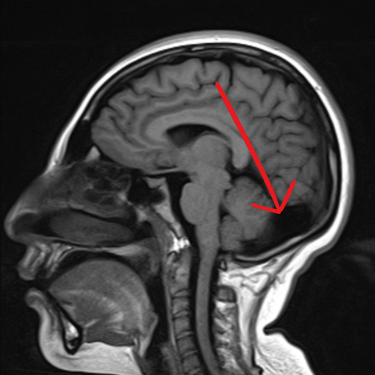

El quiste aracnoideo suboccipital es una lesión benigna de origen congénito, formada por una acumulación de líquido cefalorraquídeo entre las membranas aracnoideas. Aunque en muchos casos puede ser asintomático y detectarse de manera incidental, también puede producir cefalea, mareos, alteraciones del equilibrio o compresión del cerebelo y tronco encefálico. La resonancia magnética (RMN) es el estudio de elección, ya que permite definir la localización, tamaño y sus efectos sobre estructuras adyacentes. Este diagnóstico es clave para establecer la conducta terapéutica, que puede variar entre seguimiento clínico-radiológico o tratamiento quirúrgico en casos sintomáticos o de crecimiento progresivo.